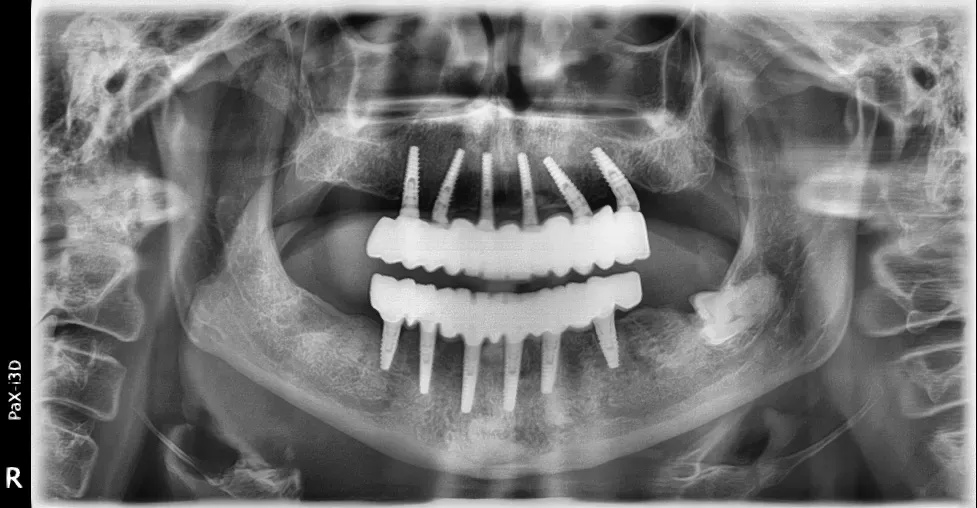

Le immagini radiografiche che seguono testimoniano alcune delle tante soluzioni tecniche che ho utilizzato per le arcate a carico immediato nel corso della mia carriera. Ogni caso presenta sfide diverse e richiede un approccio personalizzato.

Anche nei pazienti anziani con protesi mobili (dentiere) che presentano condizioni critiche dal punto di vista osseo, gli interventi di implantologia a carico immediato possono essere portati a termine con successo.

Tutto dipende dalle condizioni di salute generale e dall’anatomia residua. Non esiste un limite di età assoluto, ma solo una valutazione attenta del rapporto rischio-beneficio per ogni singolo paziente.